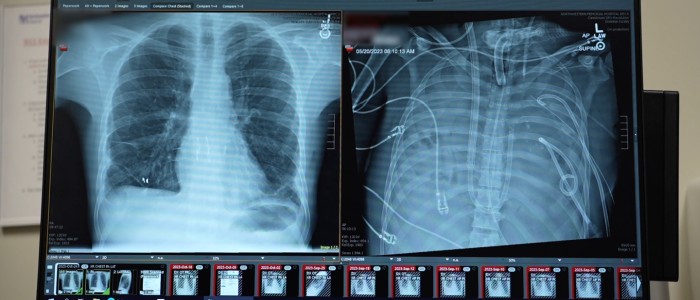

Тому Бхарат та його колеги видалили уражені легені та під'єднали чоловіка до штучних легень, розроблених командою. Система забирає кров із правого боку серця, пропускає її через помпу для насичення киснем і видалення вуглекислого газу, як це робили б справжні легені, а потім перенаправляє кров у ліву сторону серця для перекачування організмом. Ця система підтримує нормальну функцію серця та забезпечує подачу кисню.

Щонайменше тричі раніше лікарі використовували систему зовнішньої вентиляції, звану екстракорпоральною мембранною оксигенацією (ЕКМО), для насичення крові киснем та підтримки життя пацієнтів без легень доти, доки їм не було проведено трансплантацію. Але ЕКМО не є справжніми штучними легенями, оскільки вона не забезпечує належної підтримки кровотоку для серця, каже Бхарат.